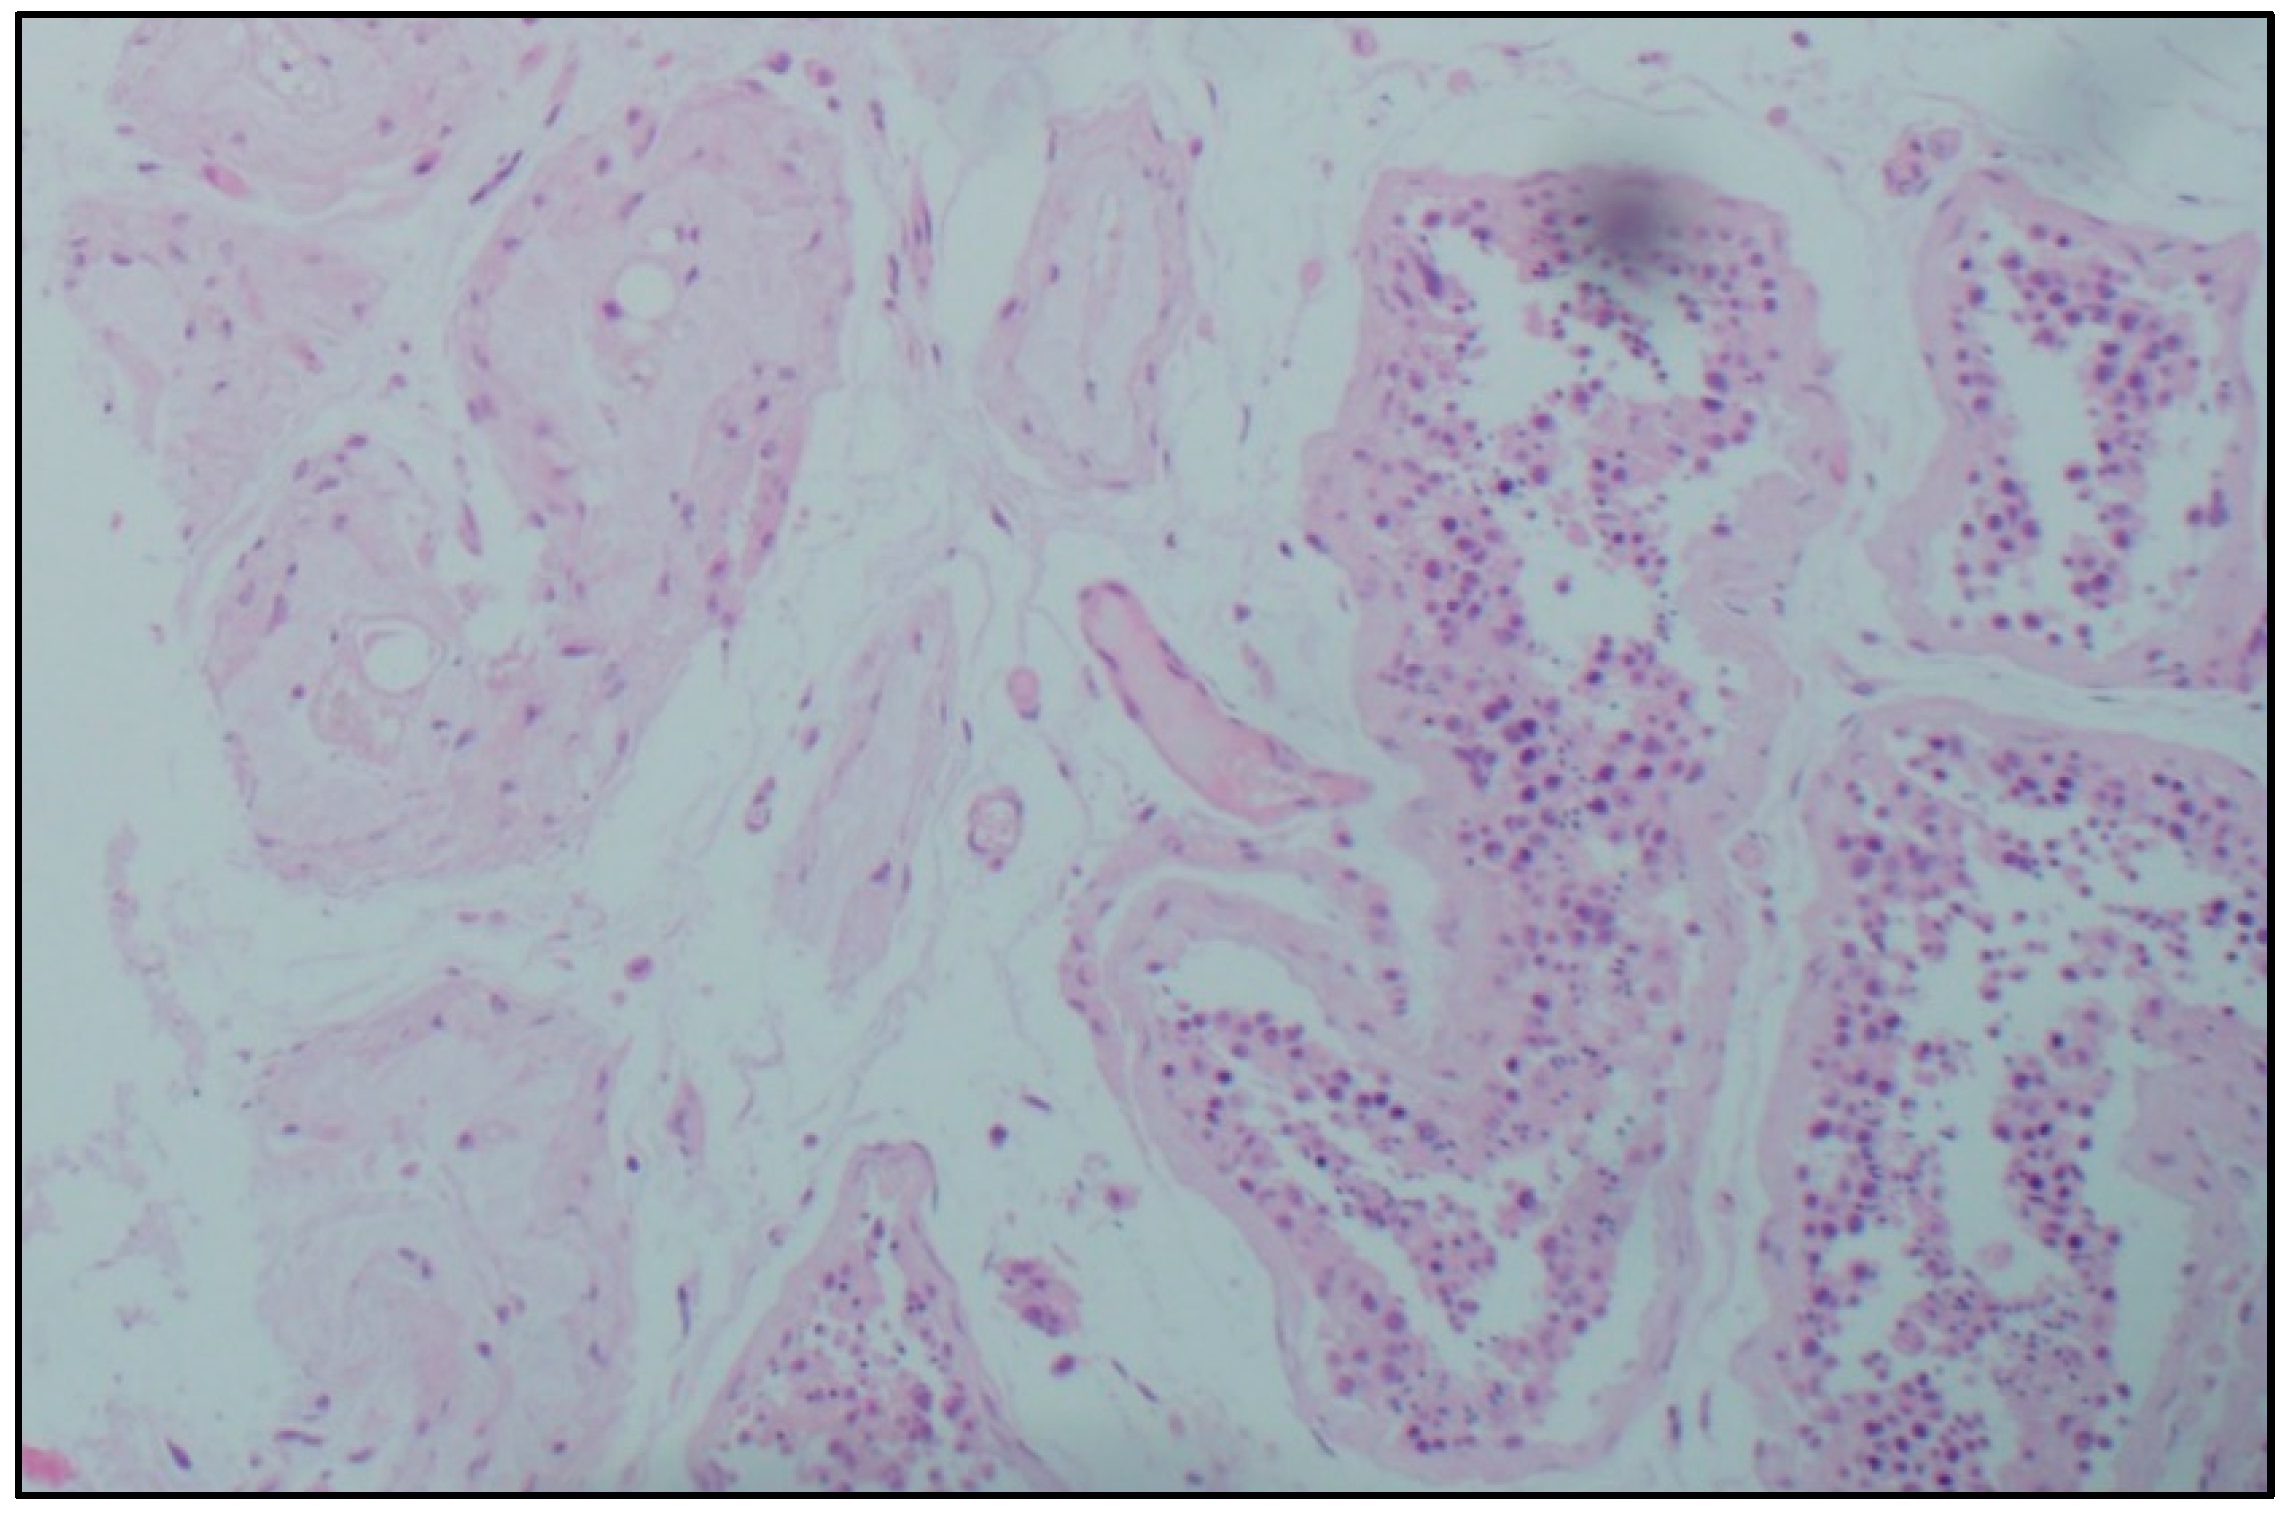

Histological examination. Microscopic analysis of the testicles of patients with confirmed coronavirus infection of different age groups revealed a decrease in the number of germ cells, and their detachment, desquamation, and conglomeration in the lumen of the seminiferous tubules in the complete absence of germ cells. Sertoli cells were absent only in some men of senile age and accompanied by a deterioration in the morphological picture of viral orchitis. In most micropreparations, thickening and loosening of the basement membrane of the seminiferous tubules, Leydig cell hyperplasia, and thickening and edema of the interstitial tissue were noted. In the intertubular space, there are signs of orchitis of predominantly viral etiology: pronounced plasmacytic-lymphocytic infiltration, single neutrophils, endothelitis, and abundant intravascular thrombosis, as well as plethora of hemocapillaries and metachromasia of their inner membrane. Lymphatic vessels are dilated, and there is a large amount of protein in their lumens (Figure 1).

Figure 1.

Morphological picture of a testicle fragment from a man with a confirmed novel coronavirus infection. Stained with hematoxylin and eosin, magn. ×100.